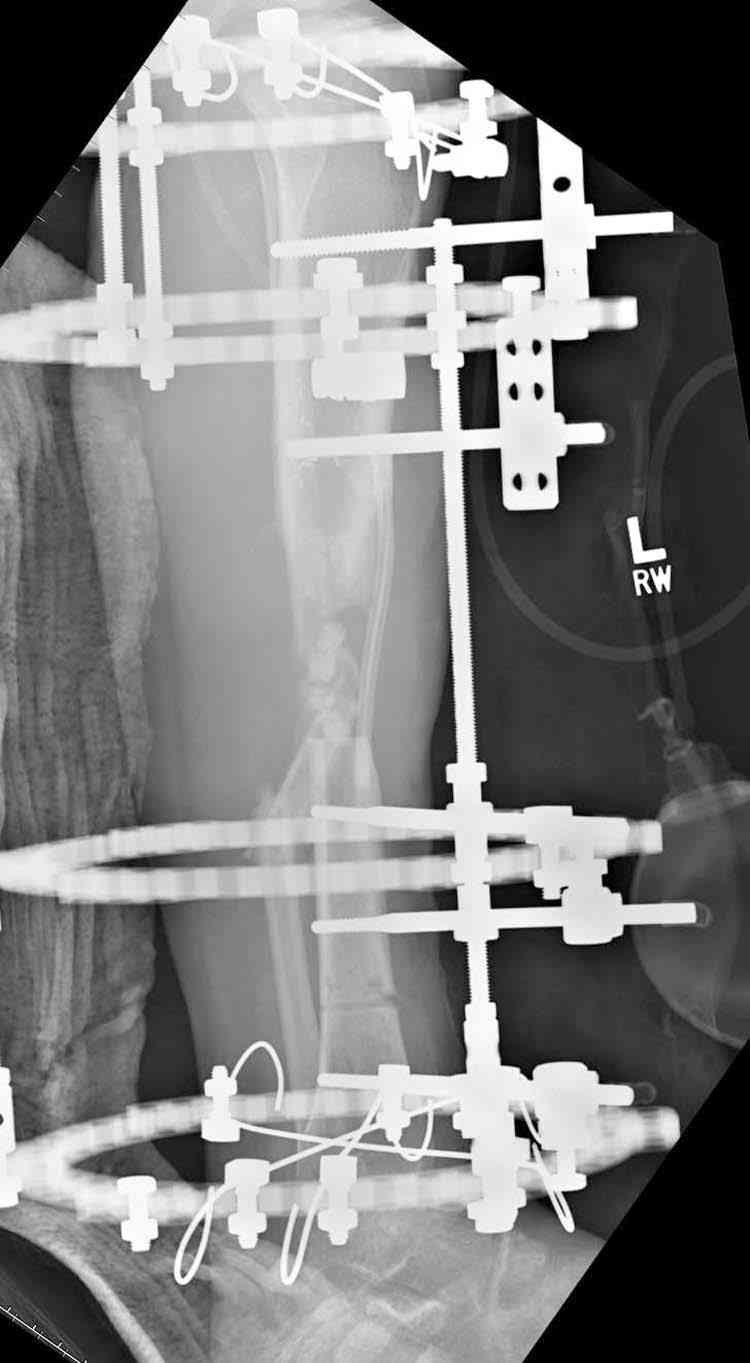

сделать поперечную остеотомию диафиза, полость заполнить antibiotic beads и начать удлинение.

Из аппаратов предпочтительно циркулярный, на дистальном фрагменте можно увеличить количество спиц.

Здесь случай, хотя не тот уровень, но принцип "удлинения после заполнения дефекта Antibiotic Beads" сохранен, можно немного увеличить количество бус.